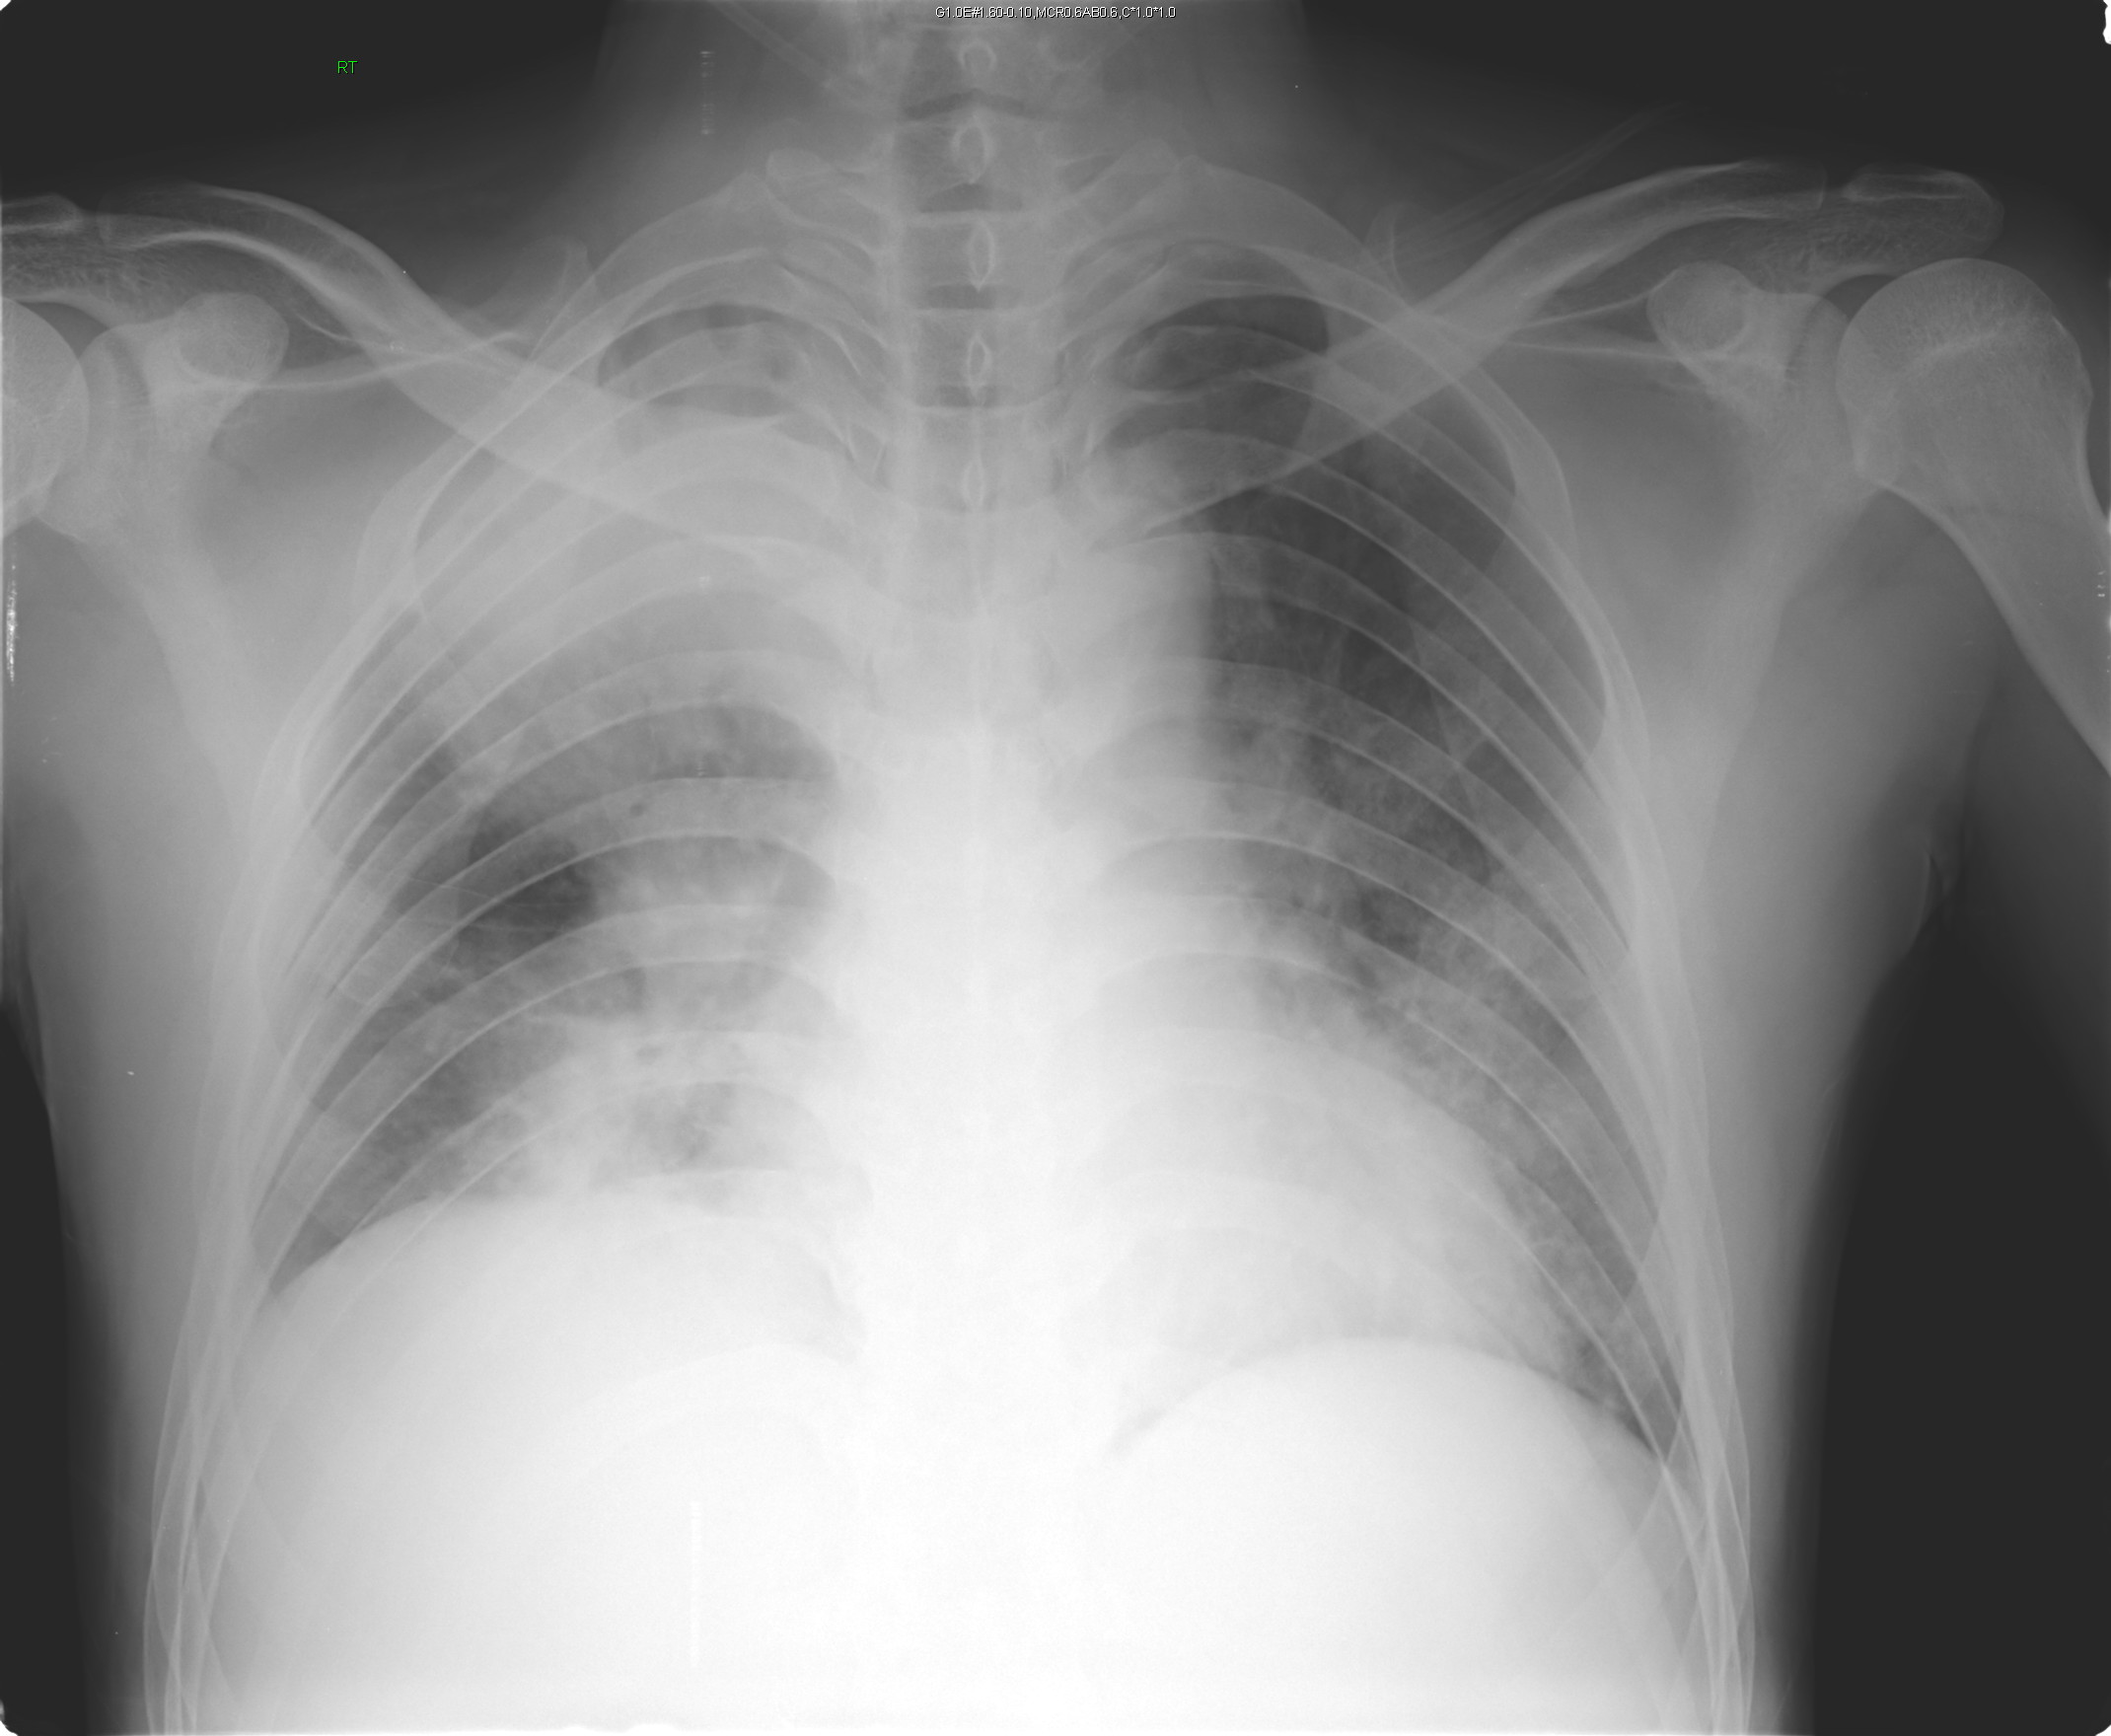

2013-04-15 chest PA